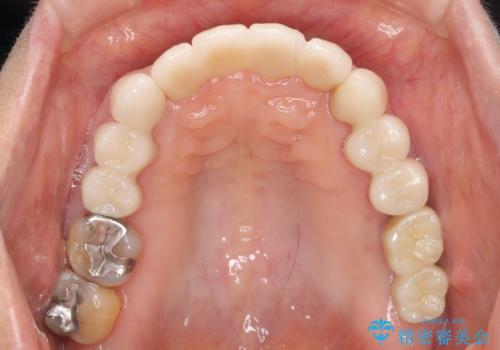

歯周病に対する全体治療

治療期間はかかりましたが、しっかりと歯周病治療・インプラント治療を行ったおかげで歯周病の状態は非常に良くなり、安定した咬合関係を確立することができました。